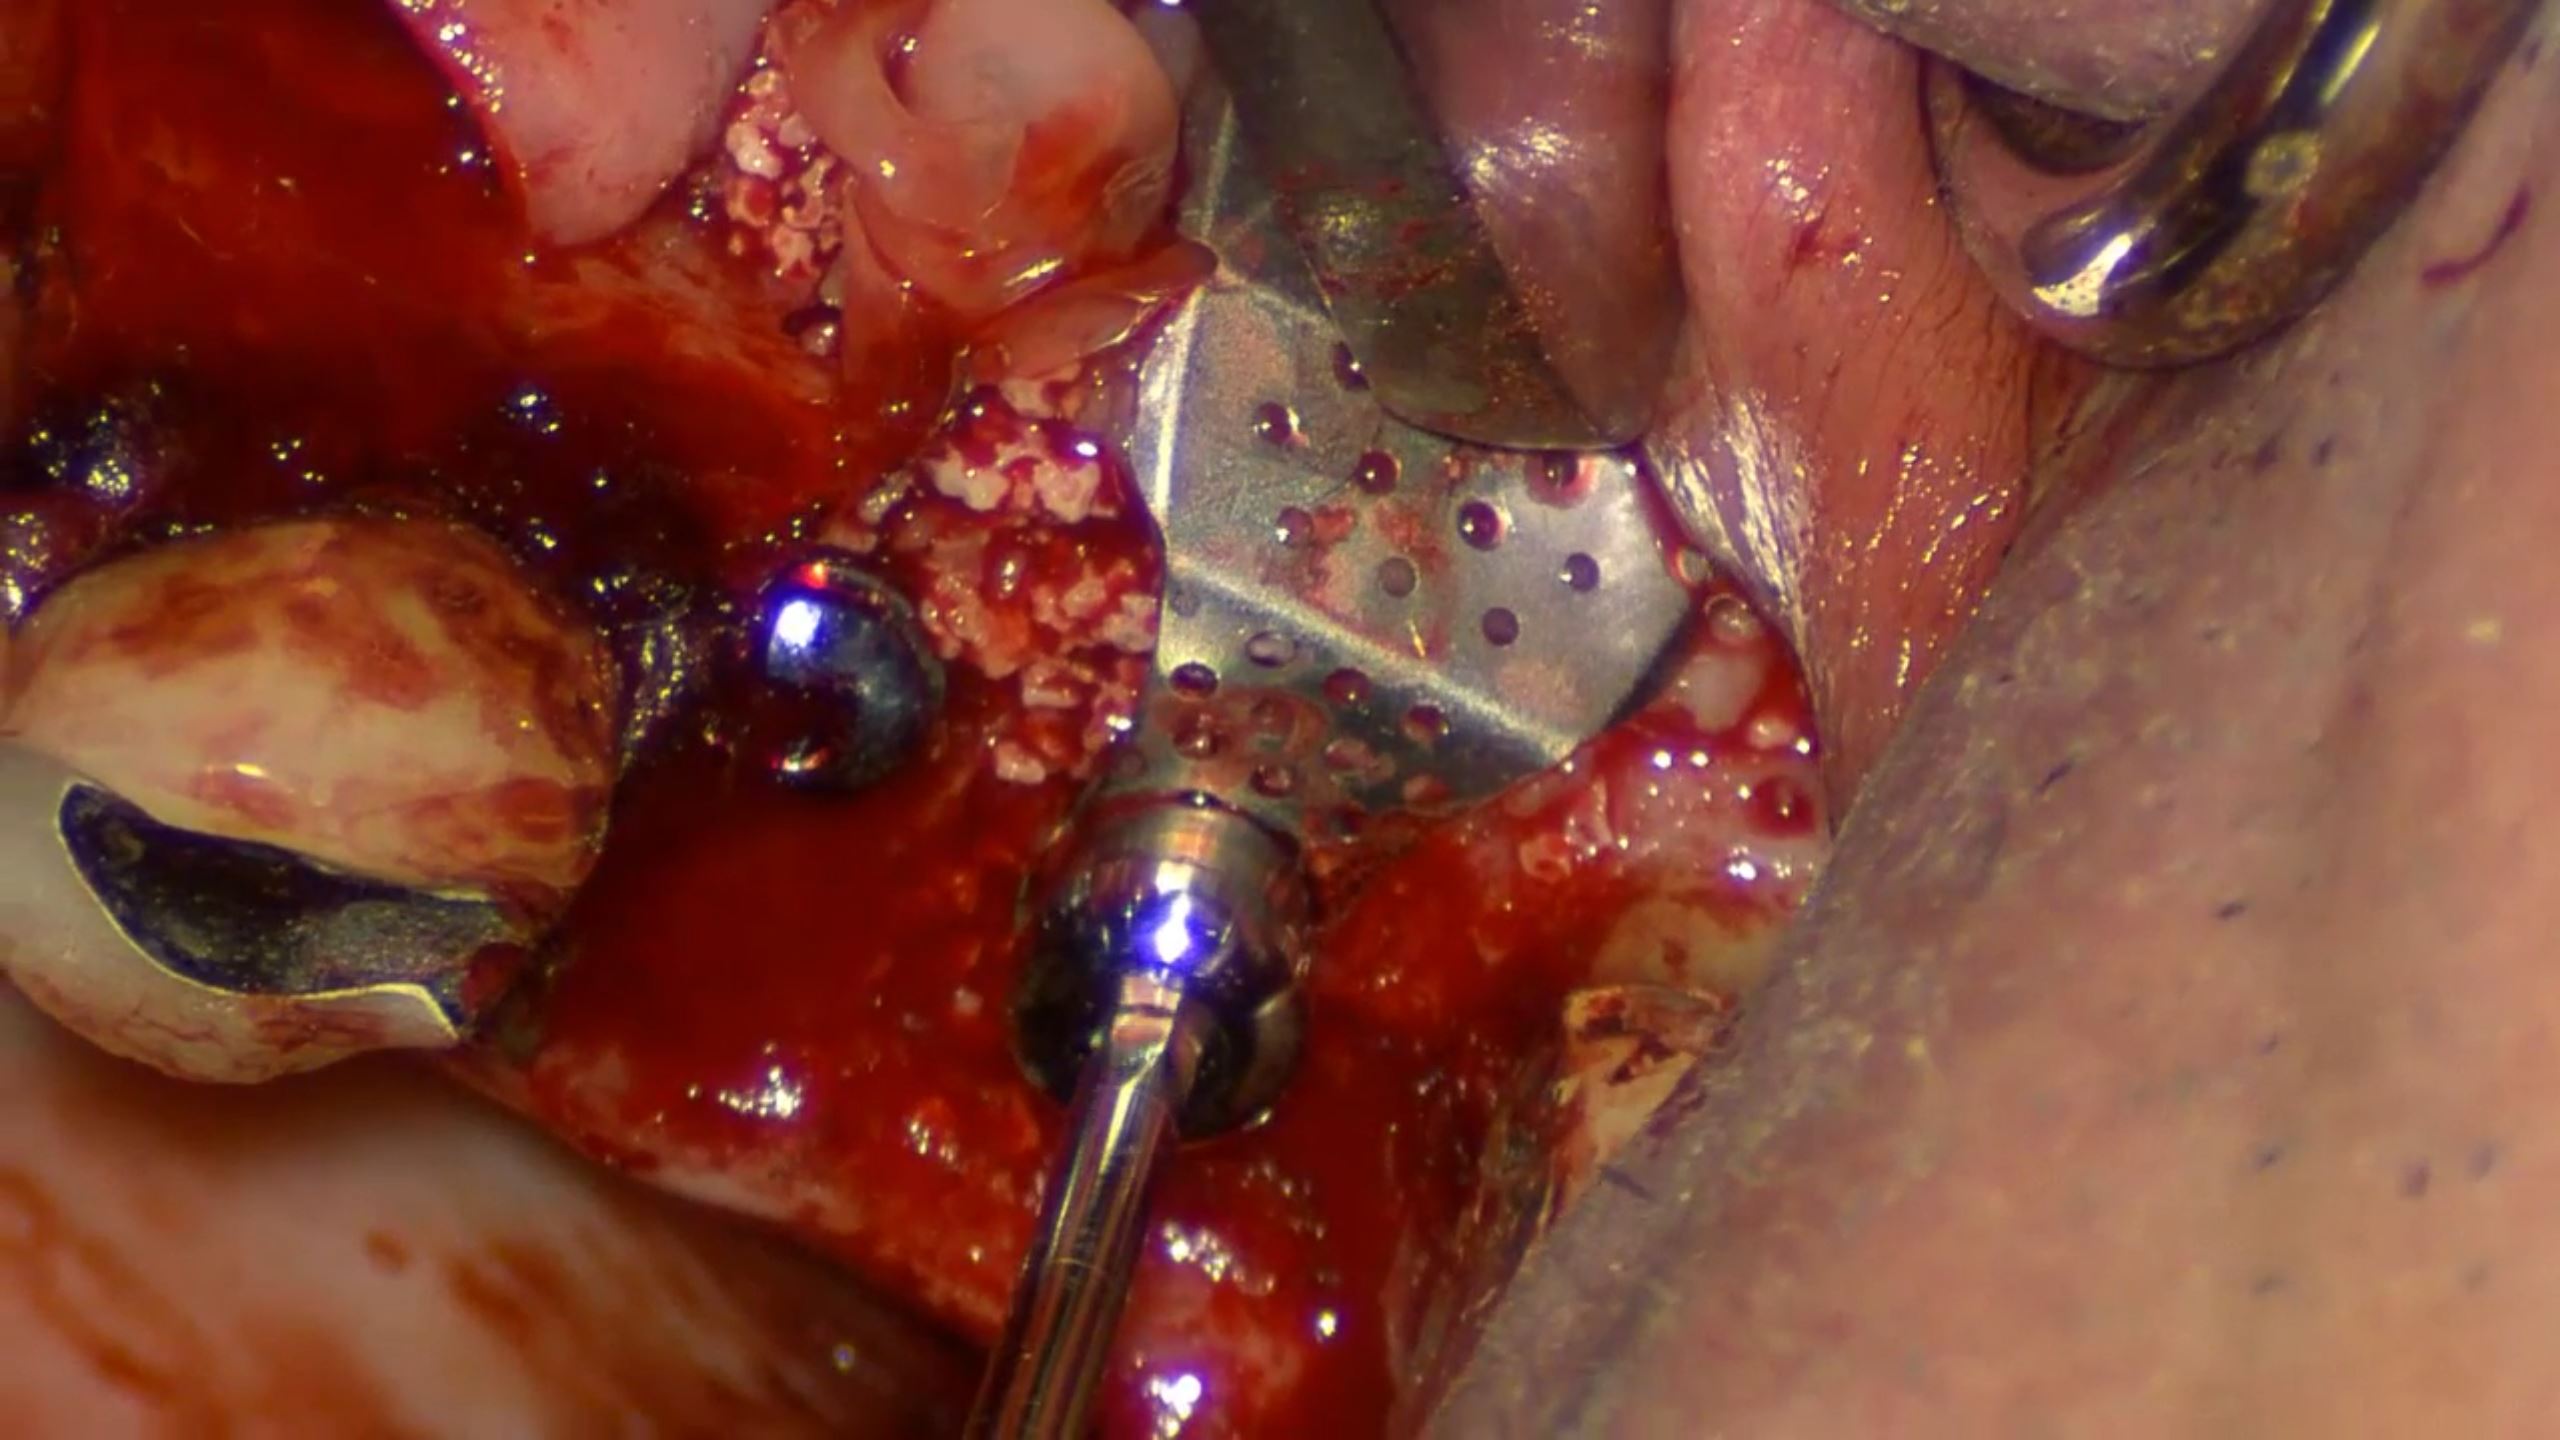

How to get a reliable ISQ!

#23,#24,#25,#26,#27,Aesthetic zone,AnyRidge,Digital,Digital Guided Surgery,Edentulous,Flapless,Immediate loading,Immediate Placement,Maxillary Posterior,MEGA ISQ,R2GATE,R2GATE Guide,R2GATE Surgical Kit(AnyRidge),video